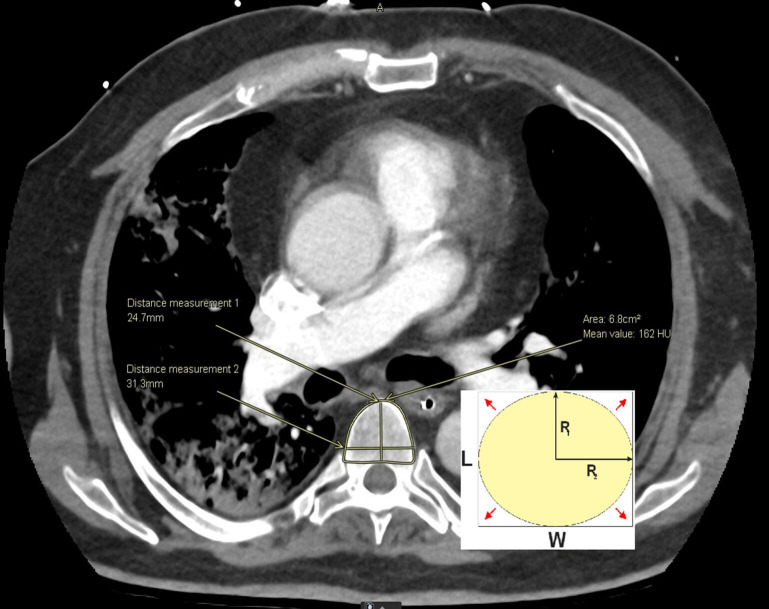

Methods: We conducted a retrospective observational study of chest CT imaging in a cohort of critically ill COVID-19 patients. We measured paravertebral SMA at T5 level and T5 vertebral body anteroposterior length, width, and area. We used linear regression and multivariable modelling to assess the association of VBA with SMA.

Results: In 48 COVID-19 patients in ICU, T5 VBA could be easily derived from simple width and anteroposterior length linear measurements. T5 VBA (measured manually or estimated from width and length) performed similarly to height (R2 of 0.22) as an adjustment variable for SMA, with R2 of 0.23 and 0.22, respectively. Gender had the strongest correlation with SMA (R2 = 0.28). Adding height or age to a model using gender and VBA did not improve correlation.

Conclusions: Gender and estimated VBA from simple linear measurements at T5 level on CT images can be utilized for adjustment of SMA without the need for height. Validation of these findings in larger cohorts of critically ill patients is now needed.